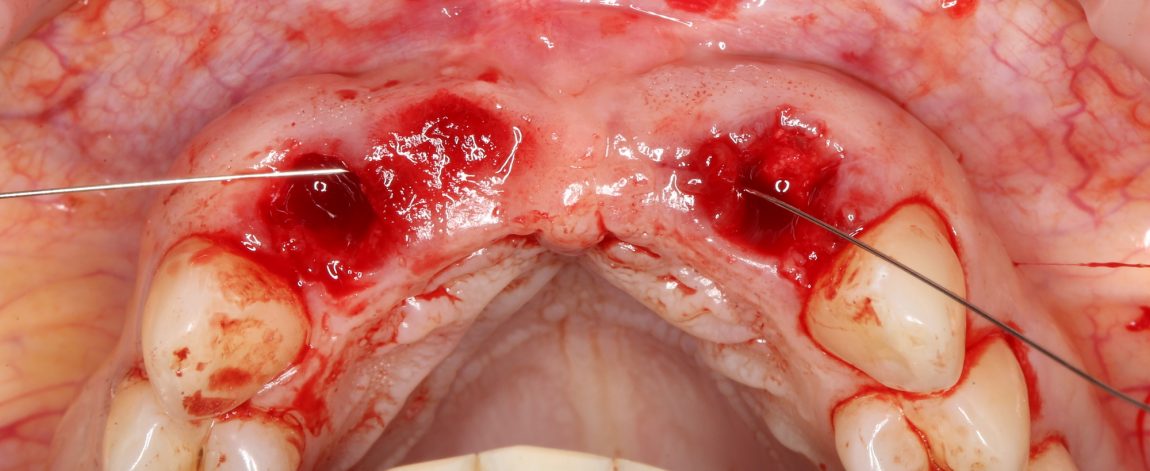

В процессе подготовки лунки под имплантаты, мы обратили внимание на следующий момент: между финишным диаметром аналога имплантата (3.4 мм) и вестибулярной стенкой лунки удалённого резца остаётся пустое пространство. Маловероятно, что костная стенка такой толщины уйдёт в небытие, но у нас есть пример атрофии в области центральных резцов — там кость ушла. Поэтому мы приняли решение об аугментации лунок:

Для этого мы используем специфический ксенографт Bio-Oss Collagen, выпускаемый компанией Geistlich. Другое название, «впихнуть невпихуемое», является лучшей его характеристикой — с ним удобно работать в узких пространствах, где использование порошкообразных и гранулированных графтов затруднено.

Обратите внимание, что мы помещаем материал еще до установки имплантатов, а не после неё. Затем, упаковываем его с помощью аналога имплантата, входящего в набор Xive (при отсутствии таковых, можно использовать круглые остеотомы):

Теперь, когда пустое пространство заполнено:

можно установить имплантат. Напомню, мы выбрали Xive S диаметром 3.4 и длиной 13 мм:

Далее, мы повторяем все эти действия с лункой 12 зуба — аугментация с помощью Bio-Oss Collagen, паковка с помощью аналога имплантата, установка имплантата Xive 3.4х13 мм:

Таким образом, мы устанавливаем оба имплантата:

Наш физиодиспенсер позволяет измерять крутящий момент при установке — у нас получилось среднее значение около 20 Нсм. Этого достаточно для немедленного протезирования.